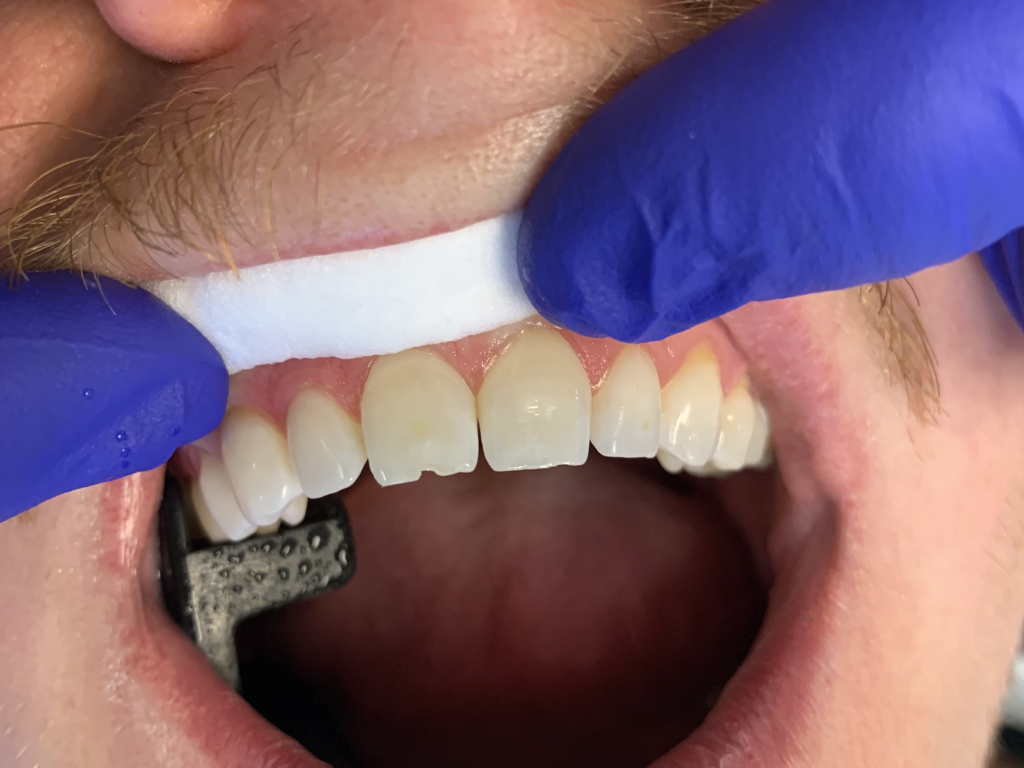

13

Anterior chipped tooth repair.